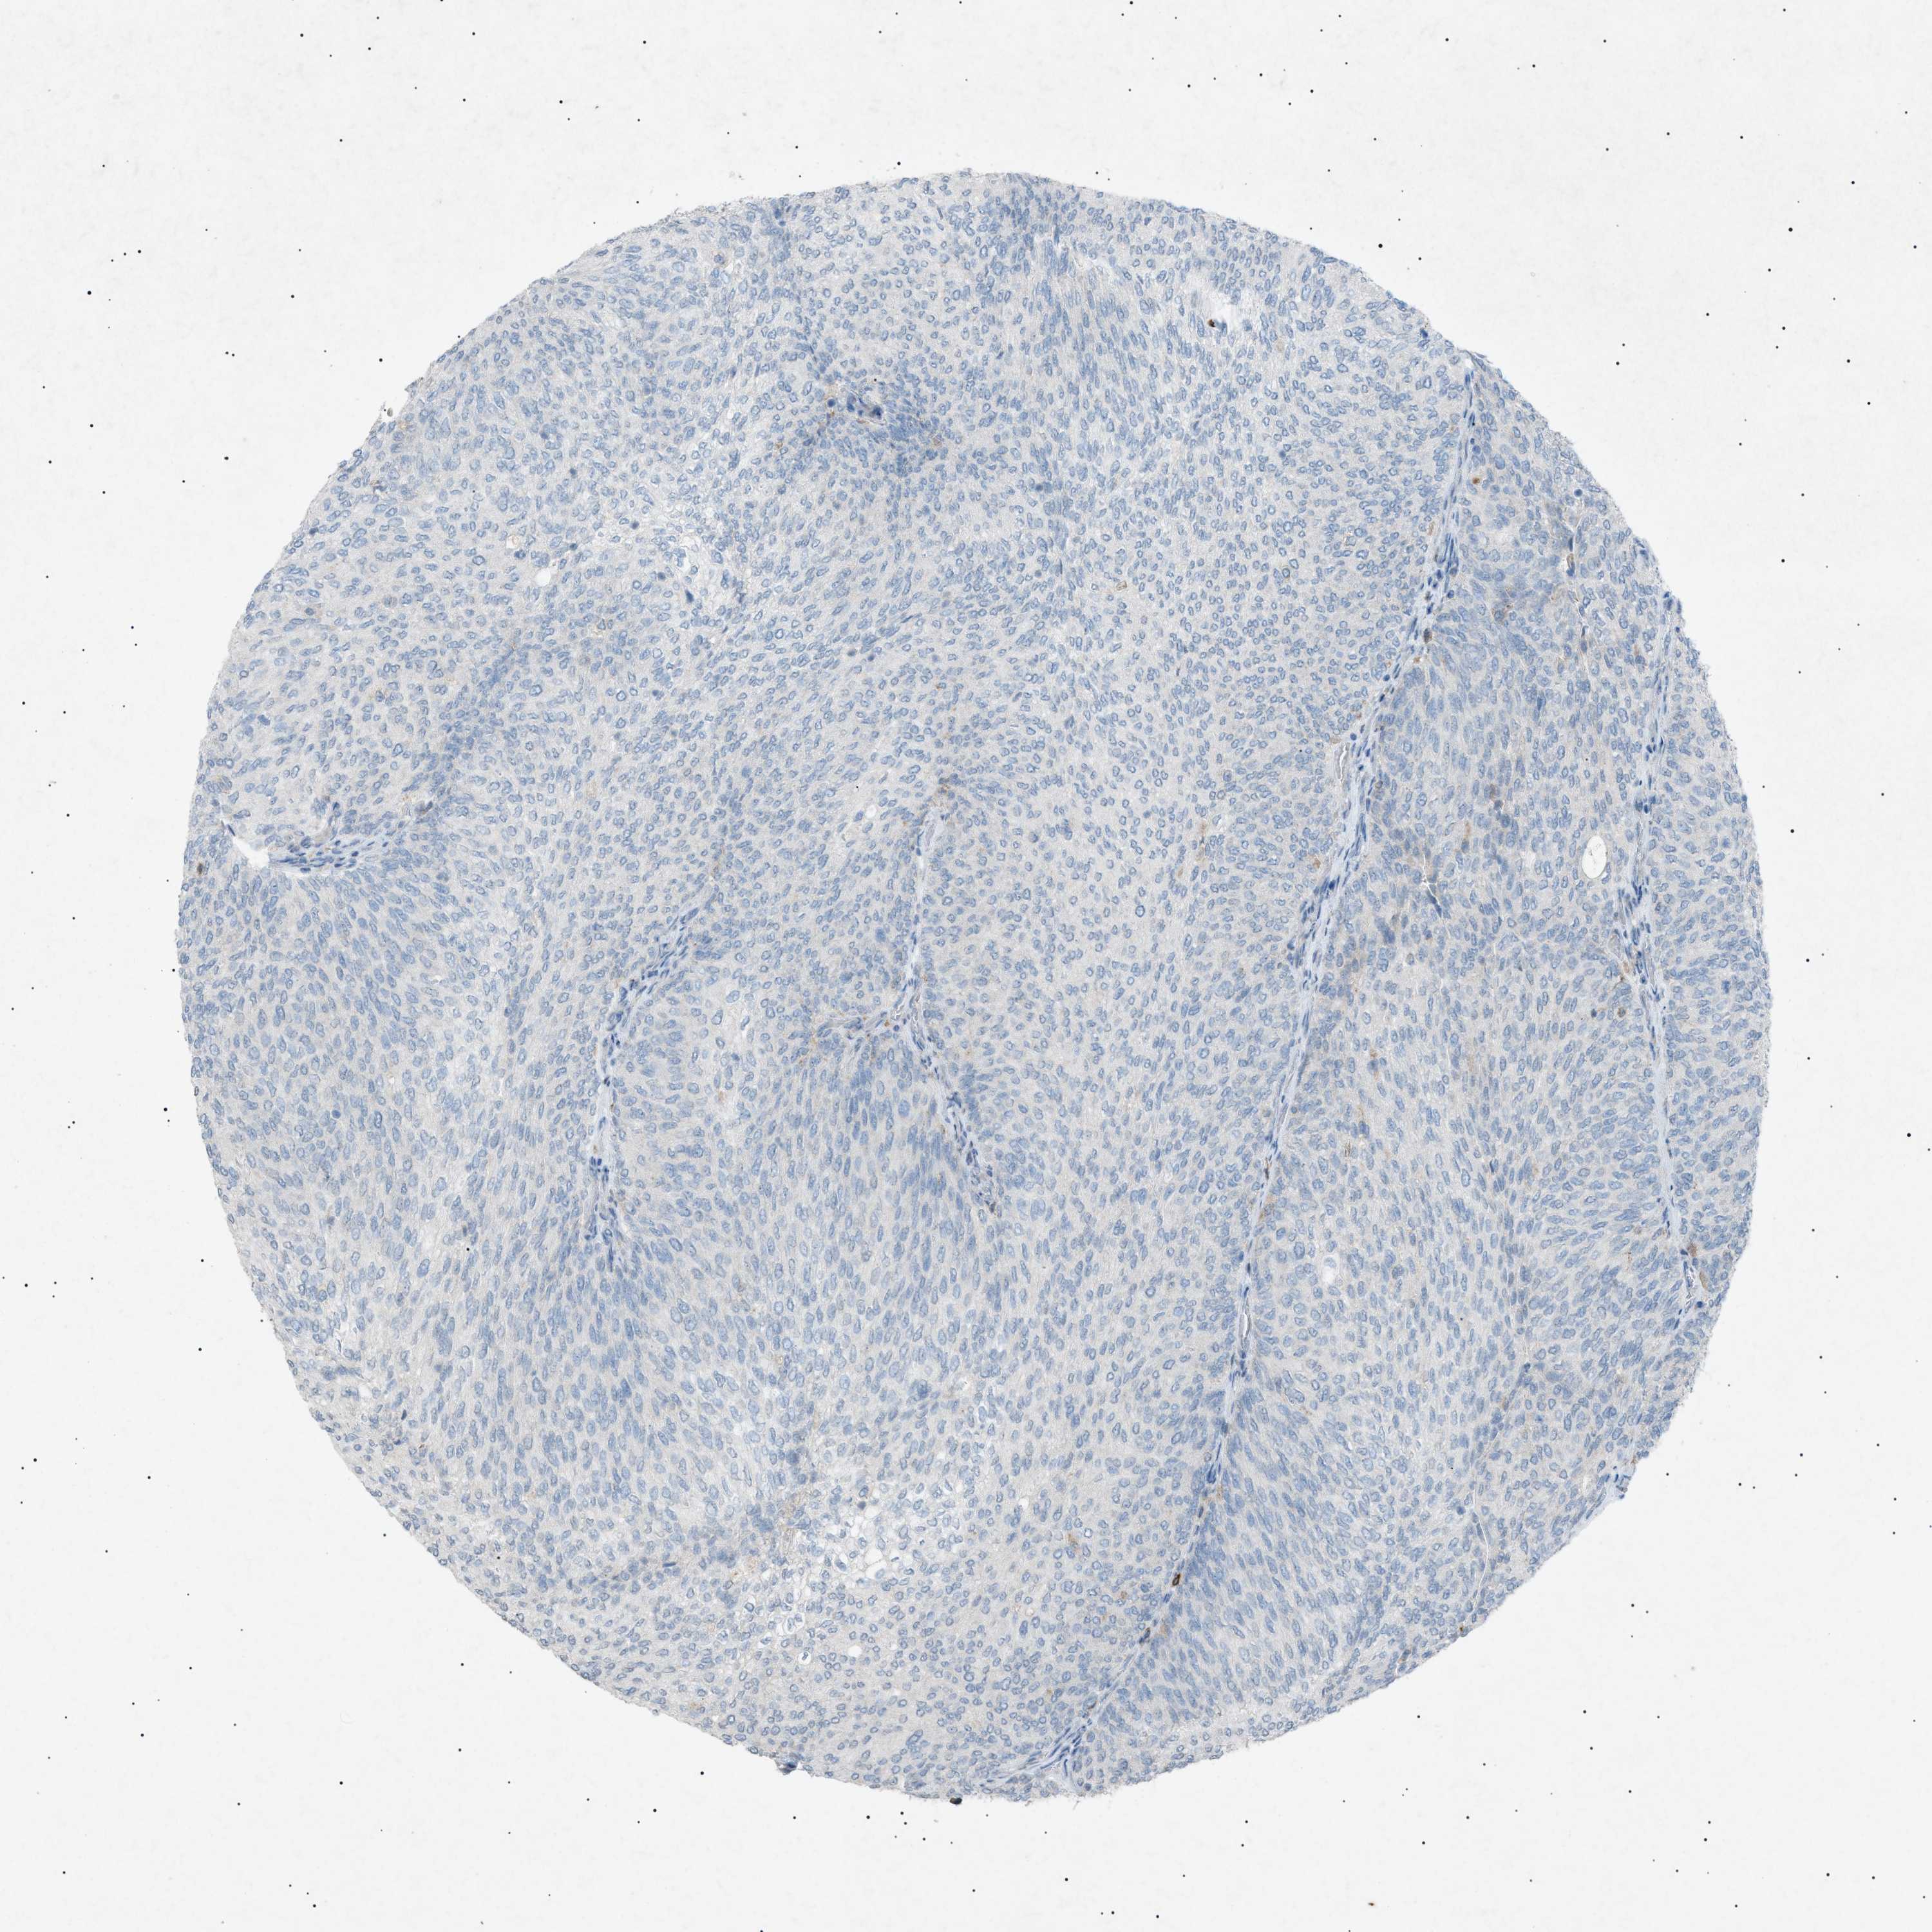

UROTHELIAL CANCER - Protein expressioni

A mouse-over function shows sample information and annotation data. Click on an image to view it in a full screen mode. Samples can be filtered based on level of antibody staining by selecting one or several of the following categories: high, medium, low and not detected. The assay and annotation is described here.

Note that samples used for immunohistochemistry by the Human Protein Atlas do not correspond to samples in the TCGA dataset.

Antibody stainingi

Antibody staining in the annotated cell types in the current human tissue is reported as not detected, low, medium, or high, based on conventional immunohistochemistry profiling in selected tissues. This score is based on the combination of the staining intensity and fraction of stained cells.

Each image is clickable and will lead to virtual microscopy that enables deeper exploration of all samples and also displays staining intensity scores, fraction scores and subcellular localization as well as patient and tissue information for each sample.

Antibody HPA001198

Antibody HPA002028

Antibody CAB016689

Antibody CAB080300

Staining

High

Medium

Low

Not detected

Intensity

Strong

Moderate

Weak

Negative

Quantity

>75%

75%-25%

<25%

None

Location

Nuclear

Cytoplasmic/membranous

Cytoplasmic/membranous,nuclear

Urothelial carcinoma, High grade

Urothelial carcinoma, Low grade

Adenocarcinoma, NOS